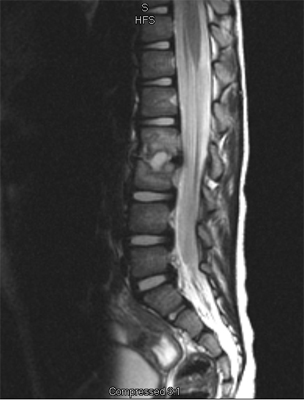

An MRI may be required if further examination of the spine is needed. An MRI machine uses magnetic waves, not X-rays, to show the soft tissues of the body. These tissues include the spinal cord, nerves, and discs. It can also evaluate spinal bones. An MRI allows your healthcare professional to look at slices of the area in question. The test may require the use of dye in an IV. Sedation or anesthesia may be needed to help your child lie still for this test.

A computed tomography (CT) scan may also be ordered. This test is best for evaluating problems with the vertebral bones. Children usually tolerate this test well, however, this test exposes them to radiation, which is significantly higher than during plain x-rays. Sometimes this test may require dye in the spinal canal fluid for easier identification of the spinal cord and nerve root anatomy. When dye is injected for this purpose, the technique is called a myelogram.